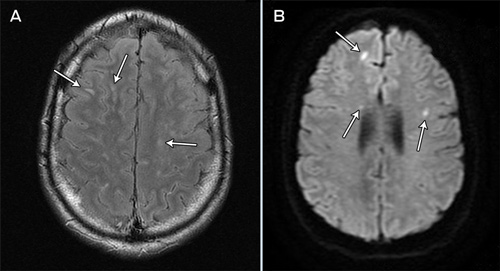

By this stage it had emerged that the patient had eaten a slug from a Sydney garden, as a dare, 7 days before presentation. An enzyme immunoassay for Angiostrongylus IgG performed on the CSF was positive. A progress MRI scan, performed on Day 26 after admission, revealed multiple foci of hyperintensity in the cerebral hemispheres, brainstem and cerebellum as well as within the spinal cord (Box 2). Several of the lesions showed restricted diffusion and some showed contrast enhancement. Pial enhancement was seen within the posterior fossa and over the spinal cord.